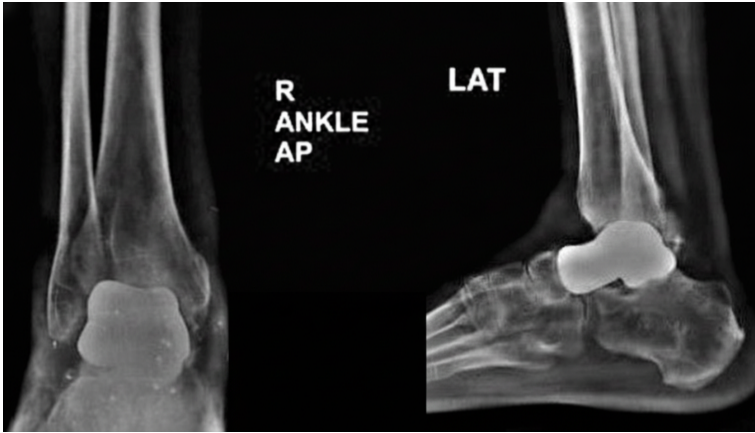

In view of progressive talar collapse and failure of the initial fixation, the patient was admitted for implant removal and definitive surgical management. The patient underwent right talar replacement using a custom-made 3D-printed titanium implant manufactured by Bonetech Medysys, following detailed pre-operative planning. High-resolution computed tomography imaging of the contralateral healthy ankle was used to generate a three-dimensional model for the fabrication of patient-specific talar prosthesis. Magnetic resonance imaging was also performed to assess cartilage thickness, which aided implant size planning. Multiple sizes of the implant were prepared. Intraoperatively, the non-viable talus affected by AVN was excised, and the ankle joint was fully exposed. All the bony fragments of talus were removed. The posterior capsule was released to get an adequate range of movement, and the appropriately sized custom implant was positioned to restore joint alignment and function. The procedure was completed successfully, with stable intraoperative joint movement, and the patient was transferred to post-operative care in a hemodynamically stable condition. Postoperatively, a below-knee slab was applied, and the patient was kept on non-weight bearing for 1 month. At the 4-month follow-up, the patient reported an improvement in pain and function. Hindfoot varus and cavus were corrected, and gait improved significantly. Both VAS and AOFAS scores showed improvement at short-term follow-up. Post-operative X-rays taken at 4-week and 4-month follow-up showed that the implant was in a stable condition (Fig. 3 and 4).

Figure 4: Post-operative anteroposterior and lateral radiographs of the right ankle at 4 months demonstrating maintained implant position and alignment following total talus replacement.